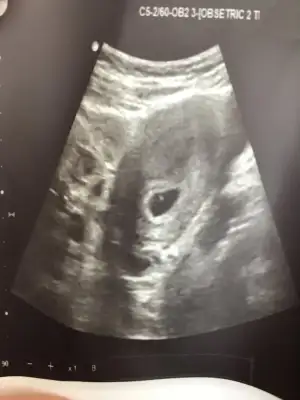

Bu varprenses gibi duruyor 7 haftaşık görüntüsü var mı?

karından ise buda evet prenses gibiBu varPasha22 6.3 haftalık birtane oğlum var 10 yaşında bakalım hayırlısı olsun

Ay kusura bakma bir öncekinde yazdım ya kafam uçmuş. 6+3 karından. Tekrar ekliyorum fotoyukızlar ah bi de kaç haftalık ve karından mı bakıldığını yazsanız

bu görüntü 7-8 haftalık civarı mıSelamPasha22 pazar göndermiştim erkek gibi demiştin. Dün tekrar gittim yeni görüntü var hala erkek mi

Karışıklık olmasın diye tekrar atayım, ilk görüntü 6+1 pazar günü olan, 2. Görüntü 6+3 salı günü olan ikisi de karından;bu görüntü 7-8 haftalık civarı mıpazar attığın görüntü peki?

seninki prenses canımKarışıklık olmasın diye tekrar atayım, ilk görüntü 6+1 pazar günü olan, 2. Görüntü 6+3 salı günü olan ikisi de karından;